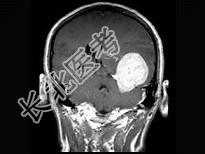

单项选择题女,34岁, 头痛数年,头颅MRI平扫及增强扫描, 最可能的诊断是 ( )

A、天幕脑膜瘤

B、星形细胞瘤

C、生殖细胞瘤

D、动脉瘤

E、三叉神经瘤